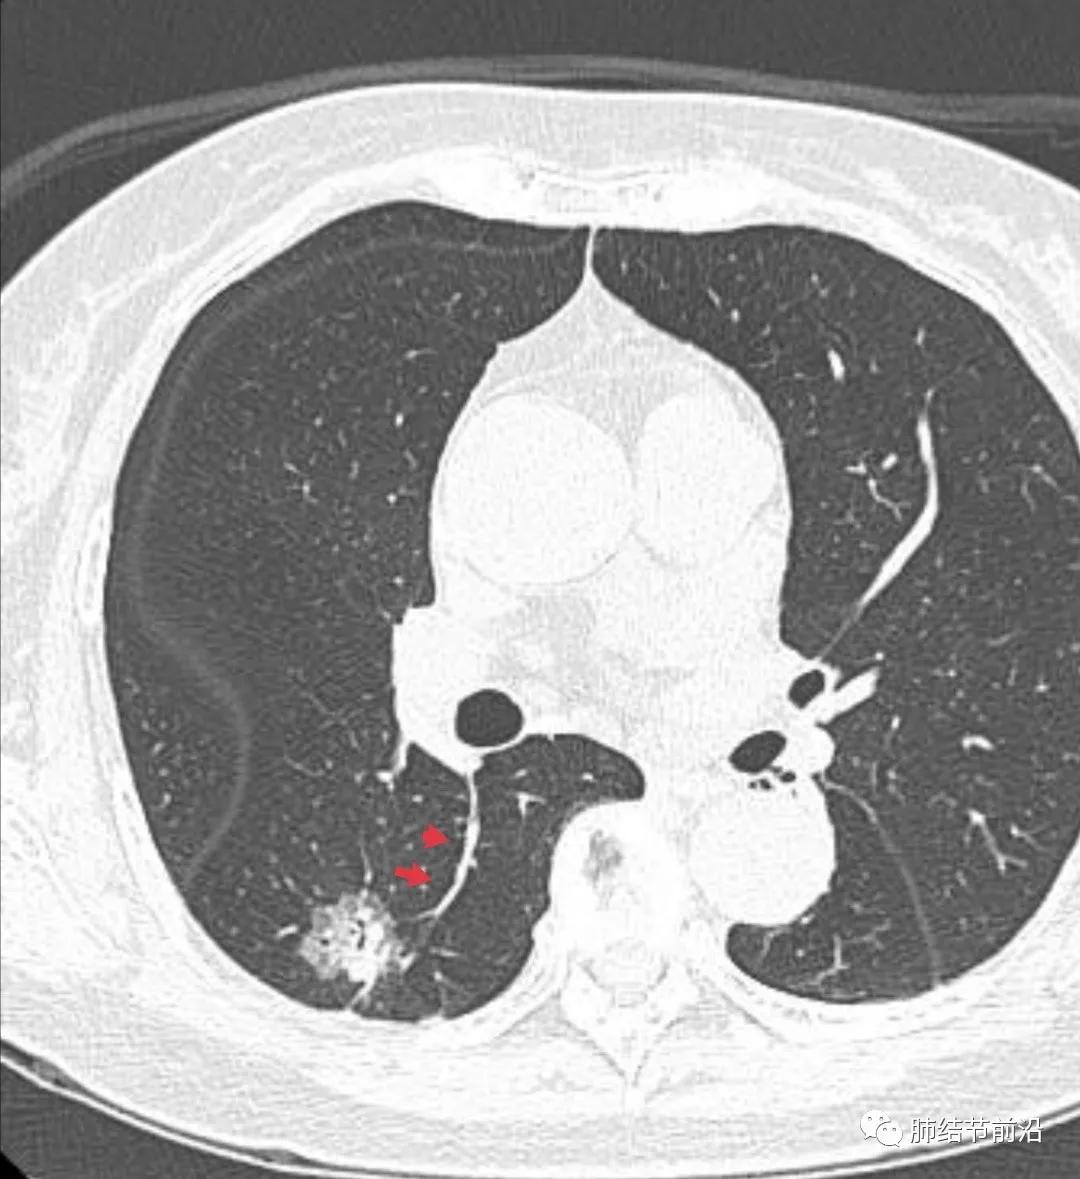

肿瘤组织需要氧供,新生血管是肿瘤的特征之一。传统的鉴别肺结节良恶性的标准之一就是血管集束征。然而在磨玻璃结节释放的血管生成因子并不强烈,新生血管不明显。则表现为诱导血管弯曲,出现明显有别于正常血管的弯曲现象,并向结节生长,称之为"血管弯"。这是肿瘤性磨玻璃/半实性结节很常见的特异性现象,出现这种表现,诊断磨玻璃/半实性结节为早期肺癌十拿九稳。“血管弯”名词引用自武汉市人民医院谭先华主任。

病例5:明显的血管弯曲指向病灶